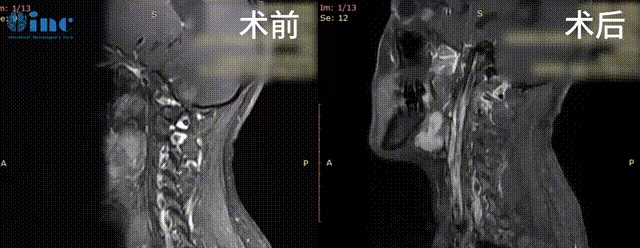

1、33岁女性-脑干颈髓室管膜留

◉手术日期: 2022年11月巴教授疑难示范手术期间

◉患者情况:33岁的郑女士2016年因晨起颈部疼痛和自感右上肢无力,行核磁检查,提示颈椎椎管占位性病变,室管膜瘤可能。然而,医生考虑手术风险过大,有可能瘫痪,因此未做进一步治疗。2年后郑女士怀孕,虽然孕后期出现下肢轻微麻木,为了腹中胎儿的健康,期间一直未行任何治疗。然而1年前患者感到症状加重,右臂没什么力气并伴有手麻症状,左臂温度感觉异常,右腿也没什么力气,左腿麻木。2022年 8 月行核磁复查,提示颈椎椎管内占位病变,室管膜瘤可能,病变较2017 年范围明显增大。为了治好自己的病,更好的陪伴着孩子的成长,郑女士决定寻求国际教授的治疗……

◉治疗过程:2022年11月23日,这台长达12个小时的高难度手术在苏州独墅湖医院顺利完成,手术时长相当于两台手术——延髓和脊随髓内。巴教授全程站立手术,参与了全场手术的国内医生无不惊叹教授无与伦比的手术技术,感叹哪怕在国际范围内,这样大的一个手术也是少见。

◉术后情况:术后一天ICU查房,郑女士意识清楚,呼吸吞咽等功能也正常,也没有出现四肢瘫痪的情况。术后12天查房,郑女士已经可以正常下地站立,肢体活动正常,除了右手稍微无力,教授鼓励她相信自己可以恢复的。

术后3个月,在郑女士传来的康复视频里,她如今已经可以正常行走,术后无力的右手已经也可以正常抓握小物体、手部运动正常。虽然动作还略显笨拙,但是对于曾经不幸罹患脑干-延髓室管膜瘤病变累及范围达15cm,曾被告知手术十有九瘫的她来说,这份笨拙就如一次新生,像孩子重学走路一般,充满着希望和勇气。